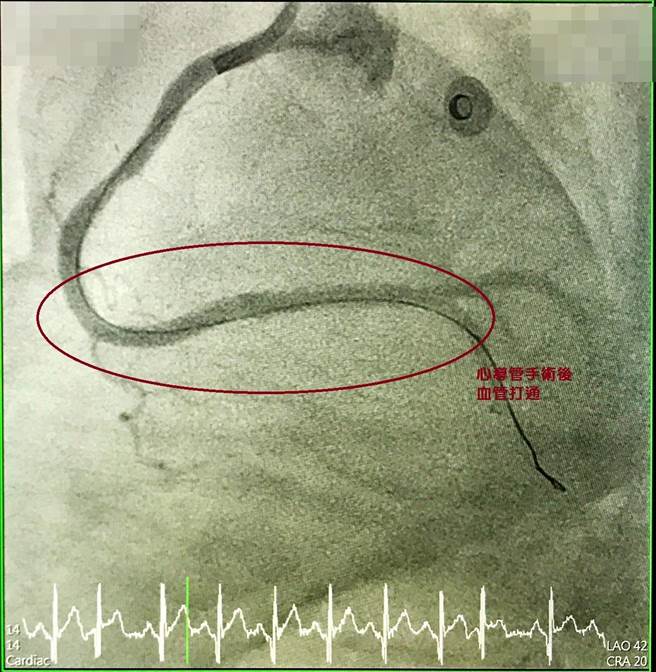

心导管手术后(血管已打通)。(大甲李综合医院提供)

冯致中医师强调,急性心肌梗塞治疗首重「黄金时间」,儘早打通阻塞血管以救回濒临坏死心肌、减少心臟受损范围,避免猝死最为重要!国外曾统计,将近一半心肌梗塞患者还没到医院心臟就停了。